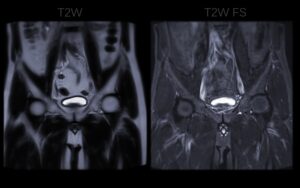

First-order intensity features

First-order intensity features, also known as histogram-based statistics, describe the distribution of voxel intensities within a lesion without considering their spatial relationship. In simple terms, they analyze the brightness levels of the pixels that make up the lesion on an MRI scan. These features provide a snapshot of the overall signal characteristics of the tissue.

These intensity metrics are valuable because different tissue types—healthy, inflamed, or cancerous—often have distinct signal intensities on MRI sequences.